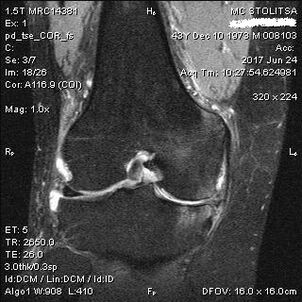

The diagnosis of arthrosis of the knee joint occurs in the office of a rheumatologist or orthopedist.The doctor examines the affected joint, palpates it, listens to complaints and asks additional questions.He carries out various tests, for example asking the patient to bend his leg or take a few steps.So, if it is necessary to clarify the stage of the disease or the nature of pathological changes, he will direct you for further studies.For example, for computed tomography or x-ray.